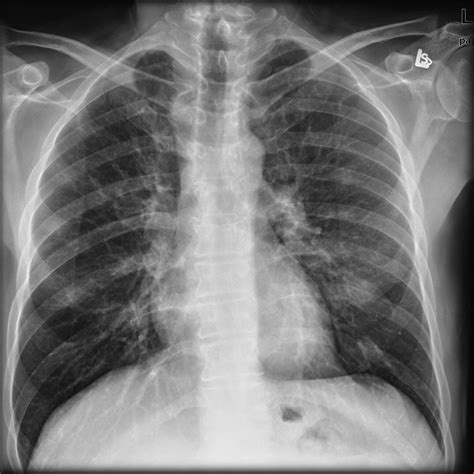

A bronchitis X ray is a crucial diagnostic tool that helps healthcare providers visualize the lungs and bronchial tubes. This imaging technique uses X-rays to create detailed images of the chest, allowing doctors to identify any abnormalities or inflammation. The bronchitis X ray can reveal:

• Inflammation and swelling of the bronchial tubes

• Presence of mucus or fluid in the lungs

• Signs of infection or pneumonia

• Structural abnormalities in the lungs

Interpreting the results of a bronchitis X ray requires the expertise of a radiologist or healthcare provider. The images are carefully examined for signs of inflammation, infection, or other abnormalities. Key findings that may be noted include:

• Increased density or opacity in the lungs, indicating inflammation or fluid buildup

• Thickening of the bronchial walls

• Presence of nodules or masses

• Signs of pneumonia or other respiratory infections